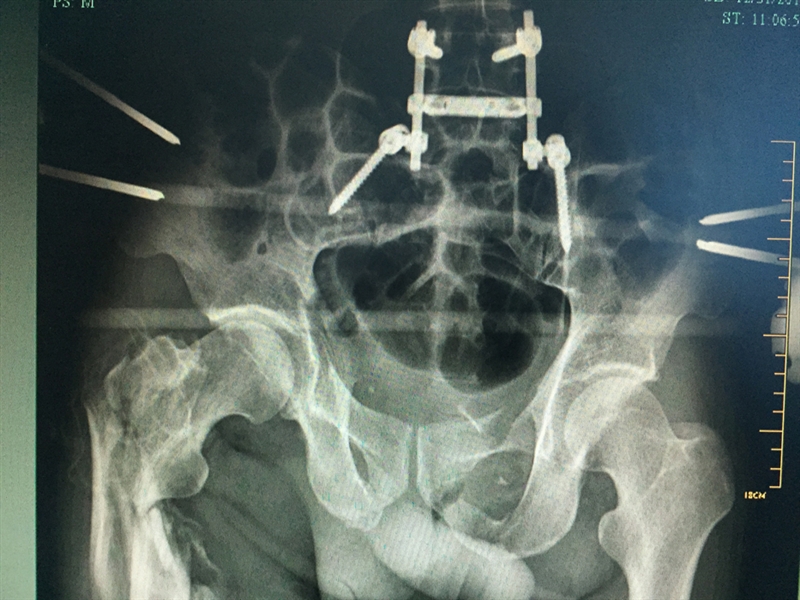

??? 說起張成的經(jīng)歷,讓人唏噓不已。2015年12月4日,46歲的張成不慎從四層高樓墜落,當場不省人事。家人立即將張成送入當?shù)蒯t(yī)院搶救,經(jīng)檢查發(fā)現(xiàn)張成血氣胸,創(chuàng)傷性濕肺,全身多處骨折,光肋骨就有11根骨折,右側股骨骨折,右側肱骨下段粉碎性骨折,最嚴重的是還有脾破裂,骨盆骨折和胸椎骨折。因傷勢嚴重,當?shù)蒯t(yī)院建議家屬將張成轉到上一級醫(yī)院。

患者入院時的X影像

??? 當天,張成被轉入衢州市人民醫(yī)院救治。到達衢州市人民醫(yī)院之后,緊張的生命接力就開始了,傷情相當嚴重,張成生命垂危,重癥醫(yī)學科(ICU)醫(yī)護團隊立即投入戰(zhàn)斗,進行搶救;生命體征一轉平穩(wěn),待命的普外科、麻醉科、手術室醫(yī)護人員馬上進行脾臟切除術;最后把接力棒交給了骨科,方智敏主任會診后深知這是一個艱巨的任務,隨即帶領診療組探討治療方案,最終制定了詳細的診療計劃,前后對患者進行了三次大手術……從12月4日至12月31日,短短一個月的時間,張成就接受了五次手術。

??? 患者術后的部分X影像